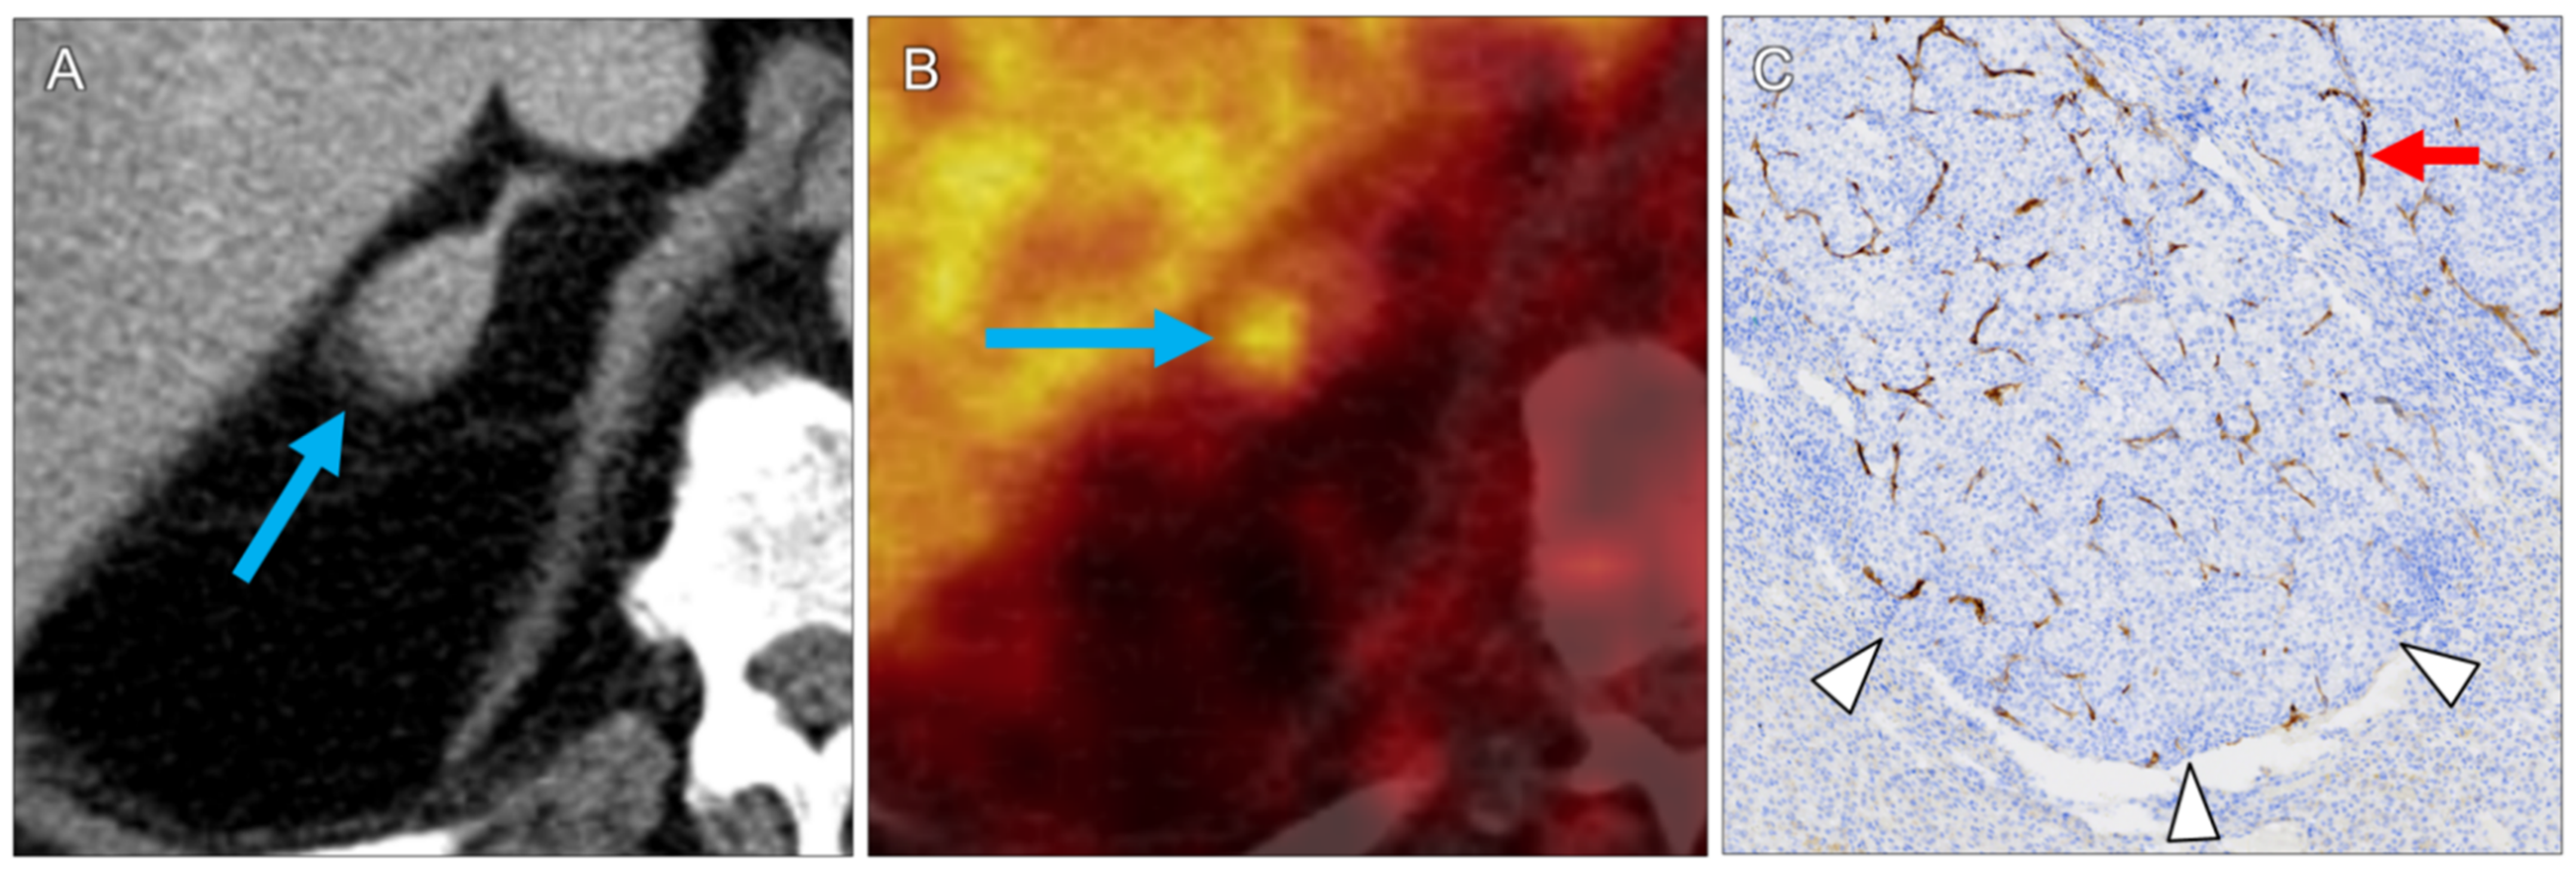

| 1 | mediastinal lymph node | 1.8 | 1.2 | 5.9 | 4.4 | 7.4 | 2 | ccRCC | 2 | 2 | 3 | 2 |

| 10 | right adrenal gland | 1.2 | 0.9 | 7.7 | 4.9 | 7.7 | 2 | ccRCC | 3 | 3 | 3 | 3 |